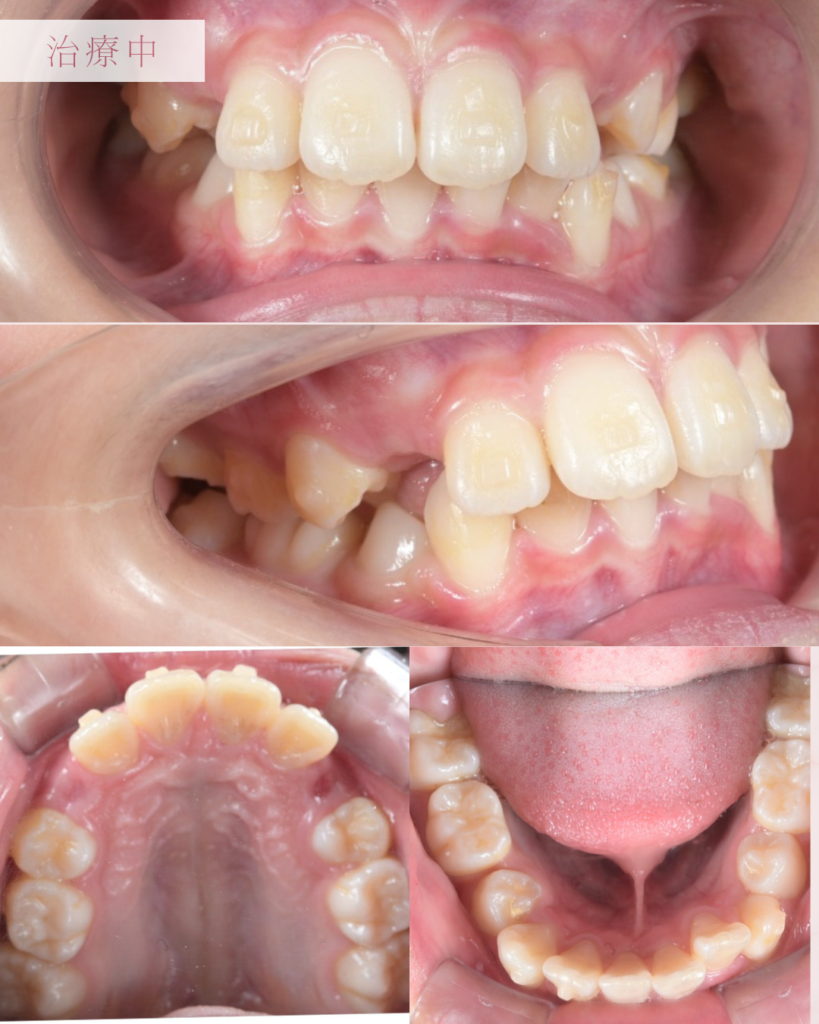

【6】治療中の様子

治療中の口腔内写真です。 透明で薄いマウスピース装置を使用するため、装着していてもほとんど目立ちません。学校生活でもお友達に気づかれにくく、違和感なく過ごしていただけました。